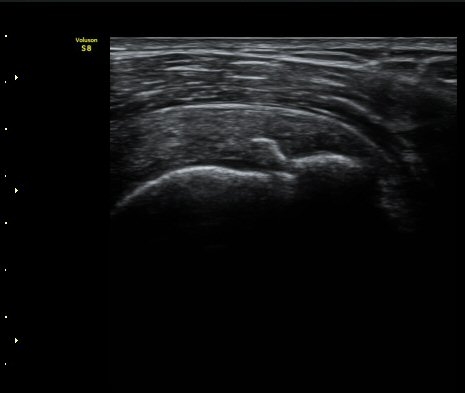

¼ºº° / ³ªÀÌ

¿©ÀÚ/ 50¼¼

ÁÖÁõ»ó

³Ñ¾îÁø ÈÄ ½ÉÇØÁö´Â ¾î±úÀÇ ÅëÁõ°ú °­Á÷

º´·Â

³Ñ¾îÁø ÈÄ ¾î±úÀÇ ÅëÁõÀÌ ¹ß»ýÇÏ¿© Ÿ º´¿ø ³»¿øÇÏ¿© ¿¢½º·¹ÀÌ °Ë»ç¿¡¼­ ƯÀÌ ¼Ò°ß ¾ø´Ù´Â ¼Ò°ßÀ» µè°í Áö³ÁÀ¸³ª ¾î±úÀÇ ÅëÁõÀÌ ½ÉÇØÁö°í Á¡Á¡ ¾î±ú°¡ ±»¾îÁ® ³»¿ø

ÃÊÀ½ÆÄ °Ë»ç